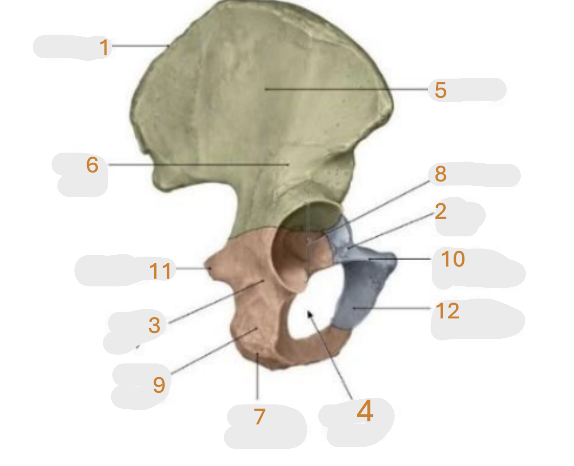

Where is the iliac crest

1

Where is the pubis body

2

Where is the ischium body

3

Where is the obturator foramen

4

Where is iliac wing

5

Where is the ilium body

6

Where is the ischial tuberosity

7

Where is the acetabulum

8

ischial ramus

9

Where is the superior pubic ramus

10

Where is the ischial spine

11

Where is the inferior pubic ramus

12